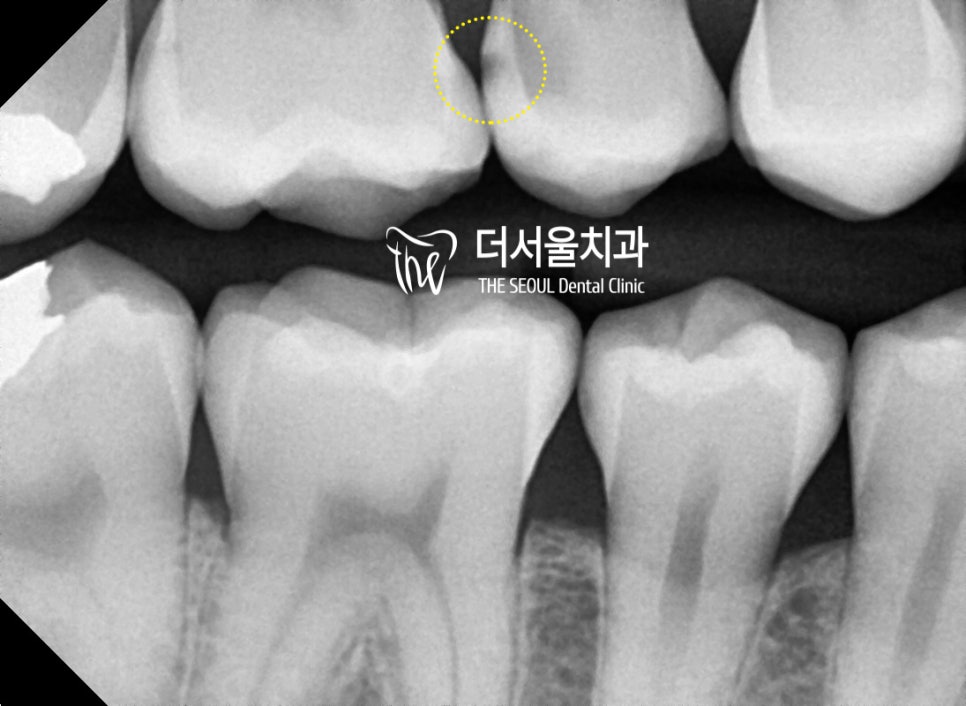

상악의 경우 눈에 잘 띄지 않는

인접면에도 충치가 발견되었는데요.

다행히 깊게 진행되진 않았기에

이곳은 비교적 간단히 개선을 할 수 있겠네요.